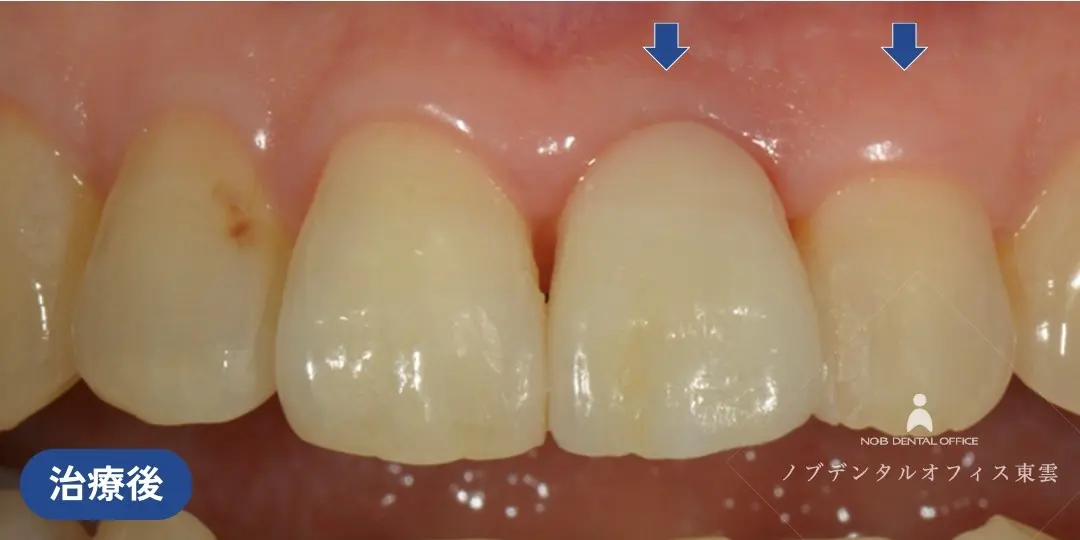

前歯をブリッジで治療した症例(40代女性)

上の前歯2本を失い、仮歯が入っている状態でした。

インプラント・ブリッジ・入れ歯の治療計画をお話しさせていただき、治療期間やリスク、強度や審美性を踏まえて、ブリッジ治療を行いました。

両隣の歯はいずれも神経がなく歯質が薄い状態でした。歯の根のトラブルが起きるとブリッジを取り外すことになってしまうので、補強もかねて根管治療の再治療を行ない、ブリッジの支台歯にしました。

セラミック完成前に仮歯に置き換え、見た目・発音・噛み合わせを調整した上で、セラミックのブリッジを作製しました。

前歯の目立つ場所でしたが、ジルコニアのブリッジで自然な仕上がりになっています。